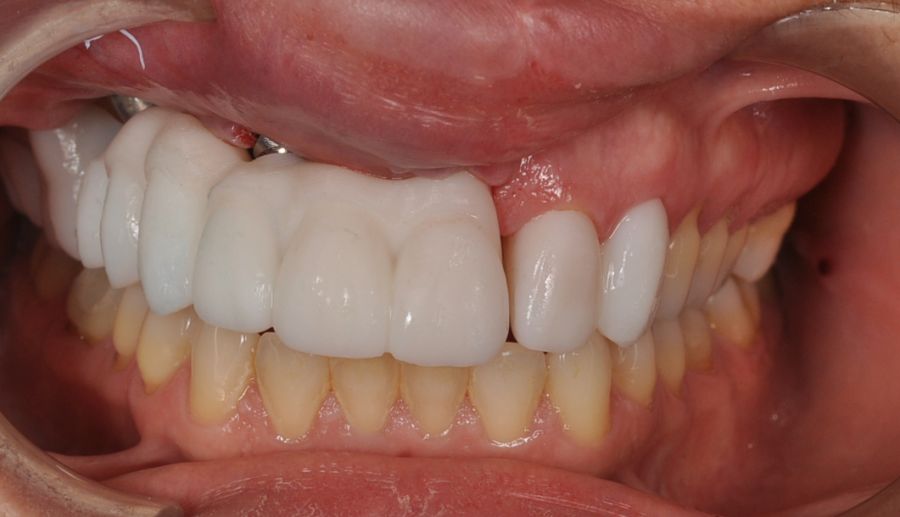

Para la fabricación de las estructuras, se eligió el óxido de zirconio monolítico como material restaurador sobre interfases metálicas en el puente implantosoportado, y coronas de óxido de zirconio monolítico en los dientes tallados previamente (1.7, 1.6, 2.2 y 2.3). Se tomaron impresiones de cubeta abierta con silicona de adición pesada y fluida (Zhermack Elite HD, Gmbh). Se realizó una prueba de pasividad analógica y el resto del proceso se confeccionó de manera digital, por lo que se hicieron pruebas estéticas de dientes impresas en 3D sobre interfases metálicas, para hacer todos los ajustes de función y estética previos al fresado del zirconio monolítico (Figuras 11, 12 y 13).

El día de la colocación de las estructuras, se arenó el interior de las coronas dentosoportadas con óxido de aluminio de 50 m y fueron cementadas con cemento de resina Multilink Ò. El puente implantosoportado se atornilló al torque indicado (20Nw) (Figuras 14, 15, 16 y 17).

En enero de 2021, el puente implantosoportado fue atornillado con un torque controlado (20 Nw), y las coronas dentosoportadas cementadas con éxito. La paciente refirió una notable mejoría en la función masticatoria, fonación y estética facial, manifestando un alto grado de satisfacción.

En el seguimiento a 4 años tras la colocación de la prótesis definitiva, no se observaron complicaciones mecánicas ni biológicas. La paciente continúa libre de enfermedad y con una correcta adaptación al tratamiento rehabilitador implantosoportado (Figura 18).